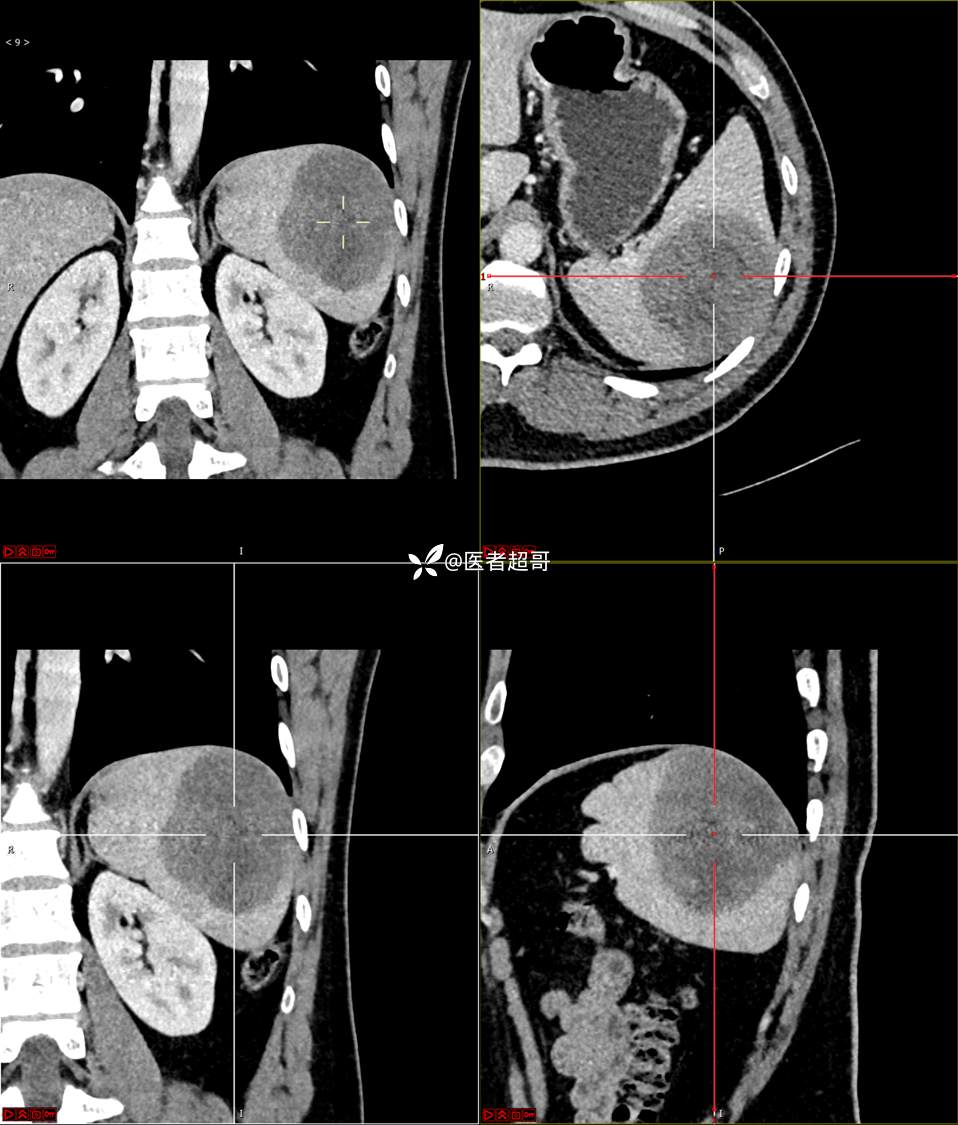

【影诊笔记738】脾脏低密度影,请诊断分析~~

男,33岁 0201215 01

主 诉:发现脾占位2月余。

现病史:患者2月余前体检行肝胆胰脾肾彩超提示脾占位性病变,未予特殊诊治,1天前于区人民医院行肝胆胰脾MR平扫提示脾脏占位性病变,左肾小囊肿,现患者无腹胀、腹泻,无恶心呕吐,无胸闷憋气等症状,今为求进一步治疗,患者来我院就诊,门诊以“脾占位性病变”收入院。患者自发病以来,一般情况可,神志清,精神可,饮食、二便正常,睡眠可,体重体力无明显改变。